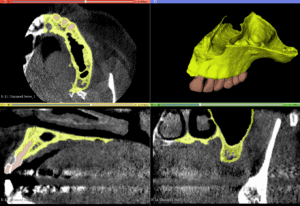

A Cone Beam CT is compiling 3D data, but it still allows us to access it only through 2d representations (slices) in a flat 2D screen. The surgeon has to read these combined 2D images and reconstruct a mental 3D structure of the surgical anatomy, certainly not an easy task to do with precision.

Note here that although the data we aquire from a CBCT are 3-dimensional, in reality the representation is still 2D: we only see it in a flat screen. To recreate a truly 3D representation you will need to 3D print the data from the CBCT. This is actually a very powerfull teaching medium, which we have often utilised in complex surgeries. 3D printing the anatomy prior to surgery allows you to test different techniques and access points with safety, before you choose the best way to go in (or sometimes to not go in at all).

A Challenging surgical case with a complex of vertical and horizontal septa in the posterior sinus. Segmentation of the 3D radiographical and optical data and 3D printing in multiple layers from AMMA Ltd Hong Kong, has allowed for an accurate representation of the anatomy where multiple surgical access approaches were tested.